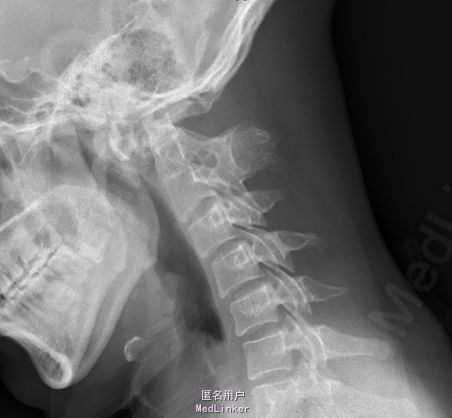

患者2年前无诱因出现后颈背部疼痛,呈胀痛性质,并伴有颈部及双上肢僵硬,休息后稍缓解,无头晕、恶心、呕吐等症状,就诊于其他医院,行MRI及颈部X片示:颅底凹陷症及寰枢椎脱位,建议患者手术治疗,患者要求暂行保守治疗,遂口服颈痛颗粒1包/tid、独一味胶囊3粒/tid、西乐葆200mg/bid,口服后症状未见明显缓解。6月前患者自觉颈背部疼痛发作频率增加,且疼痛时间延长及疼痛程度增加,同时伴右上肢麻木,并反复发作,为求手术治疗,患者来我院门诊,并以“颅底凹陷症 寰枢椎脱位”收入我科。

MRI及颈部X片示:颅底凹陷症及寰枢椎脱位

综上初步诊断:1、寰枢椎脱位;2、颅底凹陷症。